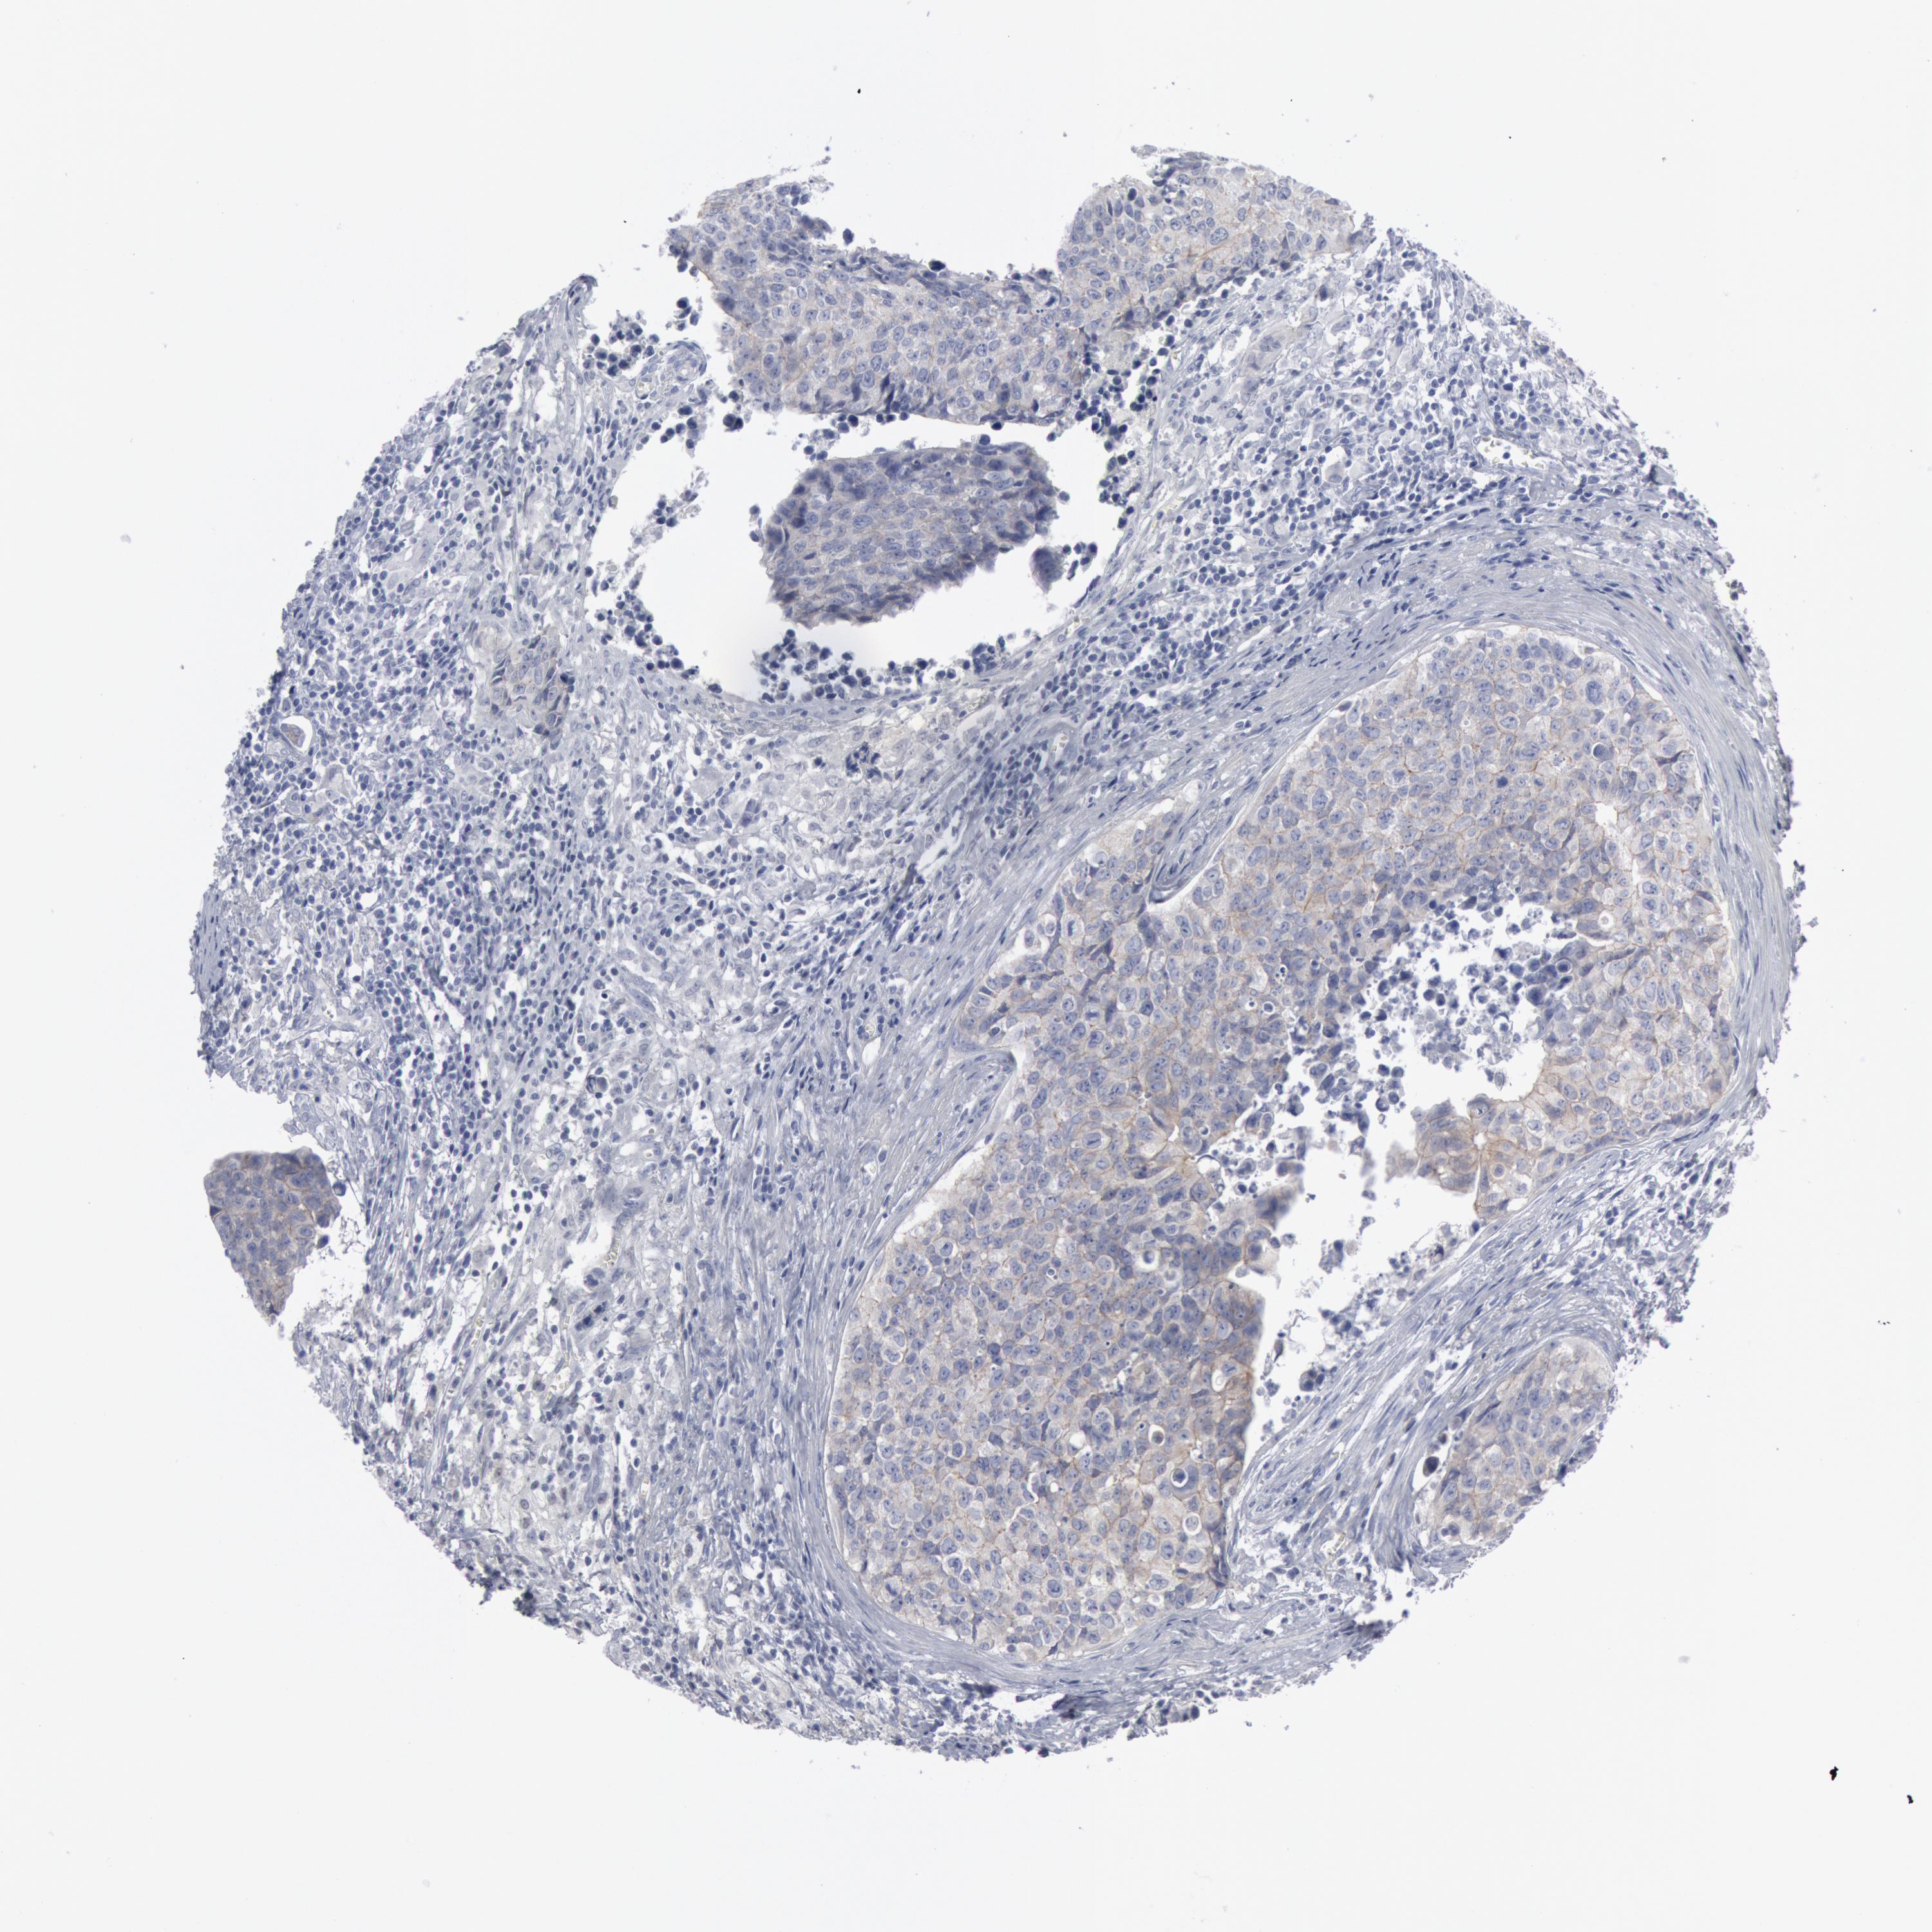

UROTHELIAL CANCER - Protein expressioni

A mouse-over function shows sample information and annotation data. Click on an image to view it in a full screen mode. Samples can be filtered based on level of antibody staining by selecting one or several of the following categories: high, medium, low and not detected. The assay and annotation is described here.

Note that samples used for immunohistochemistry by the Human Protein Atlas do not correspond to samples in the TCGA dataset.

Antibody stainingi

Antibody staining in the annotated cell types in the current human tissue is reported as not detected, low, medium, or high, based on conventional immunohistochemistry profiling in selected tissues. This score is based on the combination of the staining intensity and fraction of stained cells.

Each image is clickable and will lead to virtual microscopy that enables deeper exploration of all samples and also displays staining intensity scores, fraction scores and subcellular localization as well as patient and tissue information for each sample.

Antibody HPA001232

Antibody CAB015397

Staining

High

Medium

Low

Not detected

Intensity

Strong

Moderate

Weak

Negative

Quantity

>75%

75%-25%

<25%

None

Location

Nuclear

Cytoplasmic/membranous

Cytoplasmic/membranous,nuclear

Urothelial carcinoma, High grade

Urothelial carcinoma, Low grade

Adenocarcinoma, NOS